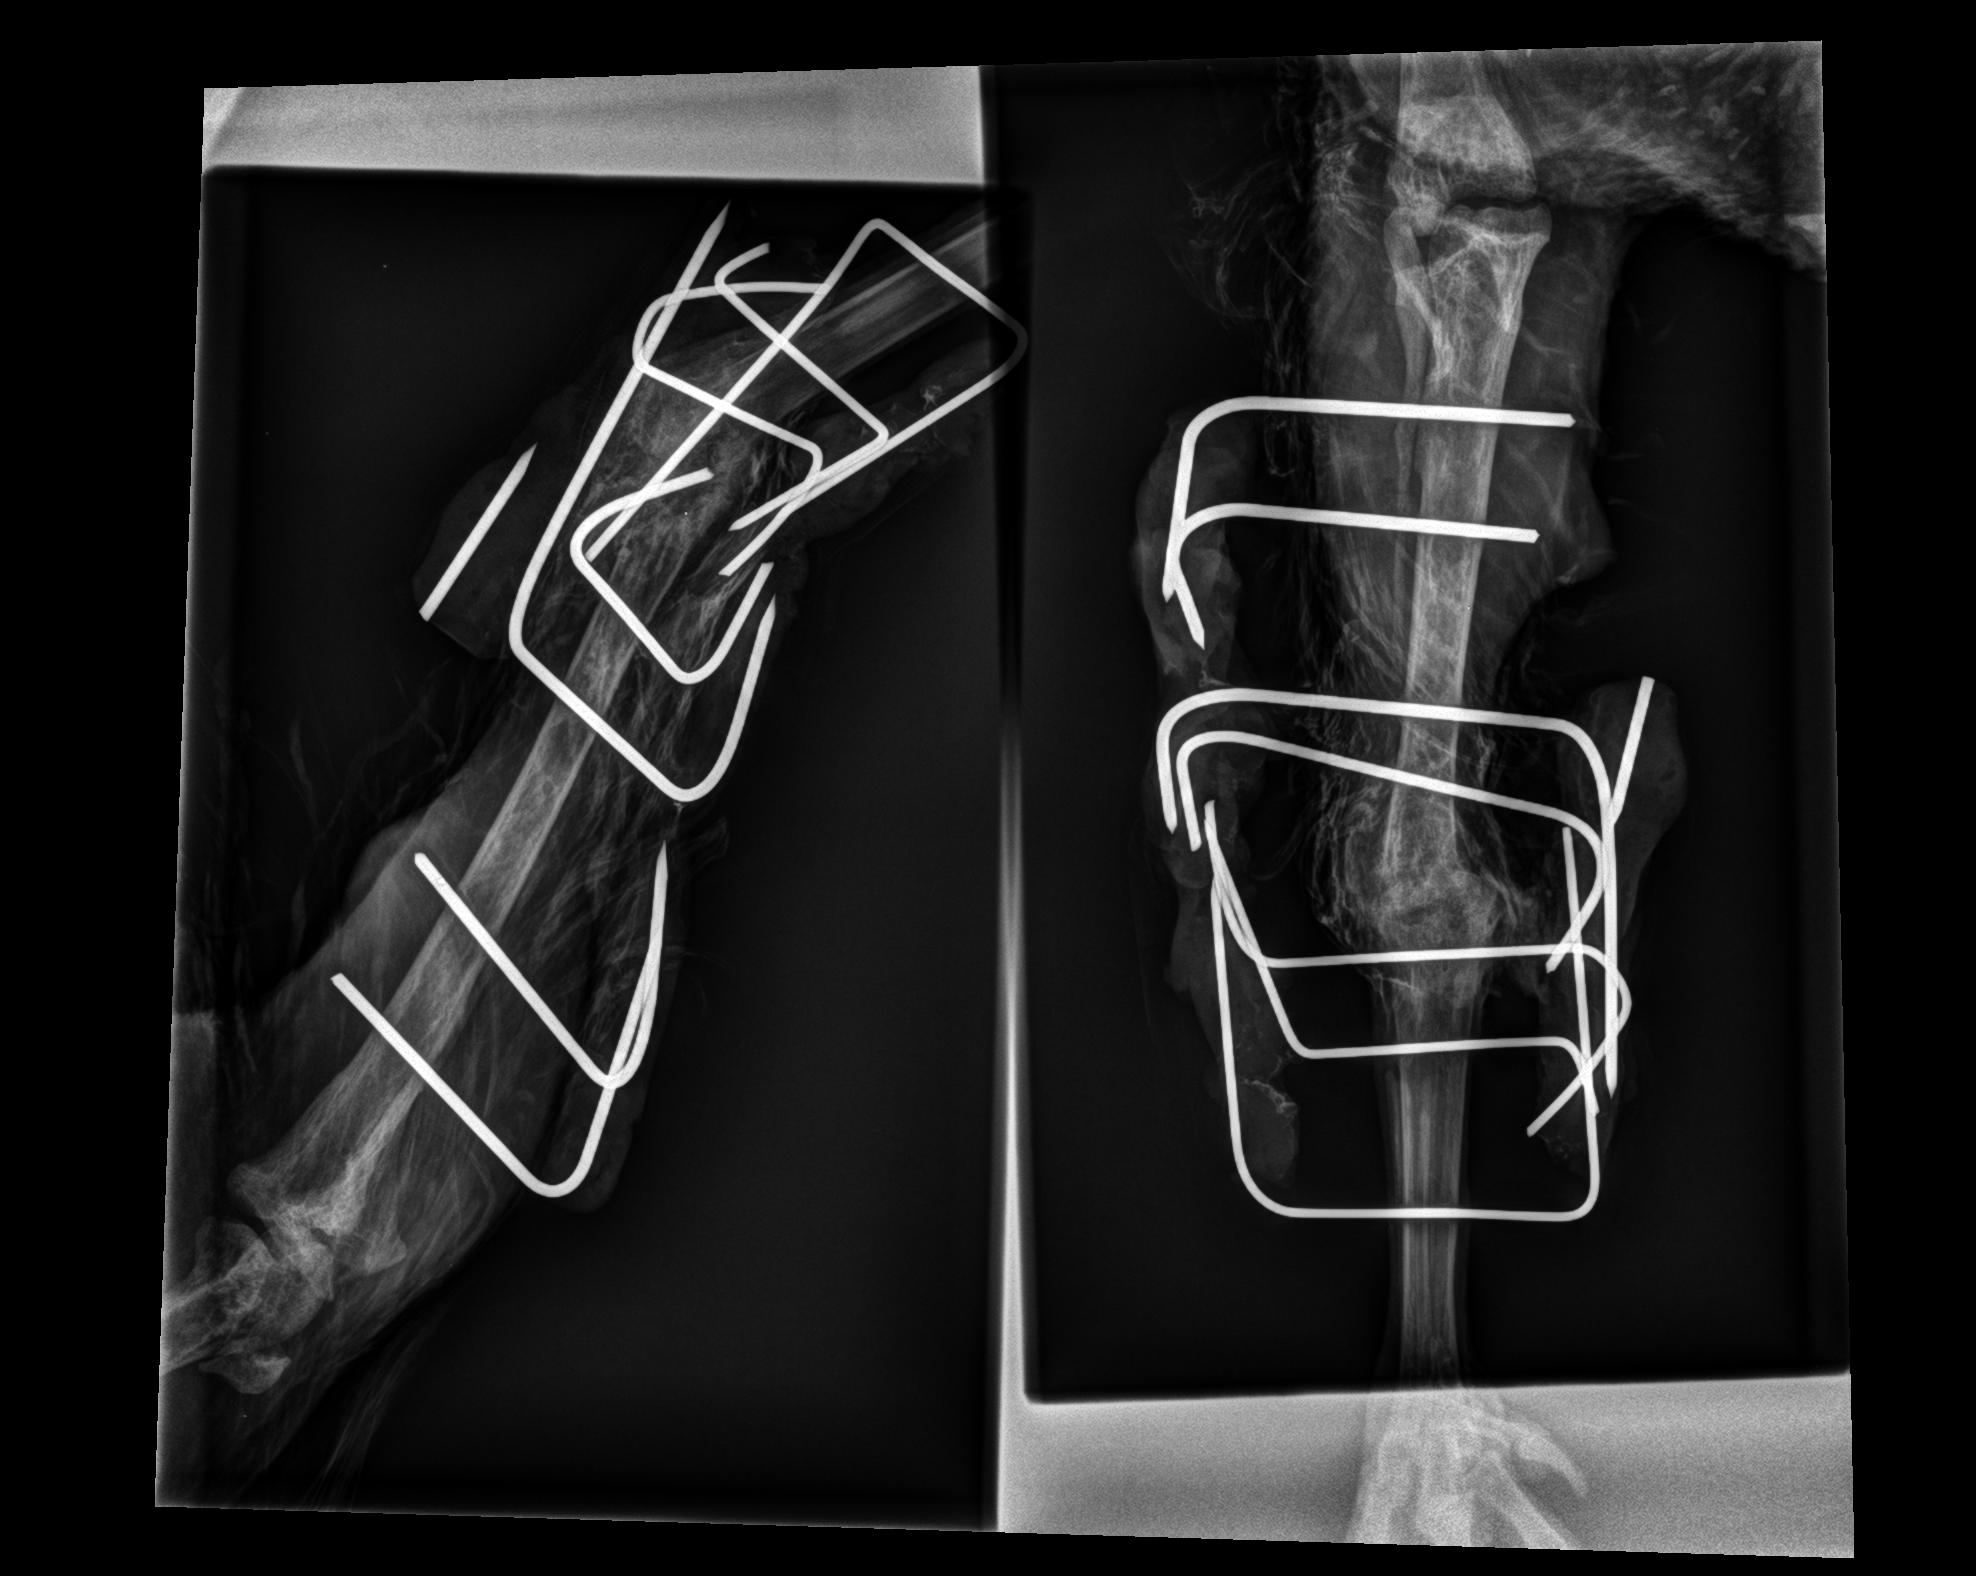

Die Knochenchirurgie verlangt die präzise Zusammenstzung der Teile um Funktion und Anatomie wieder herzustellen.

Insbesondere bei Greifvögel keine einfache Aufgabe